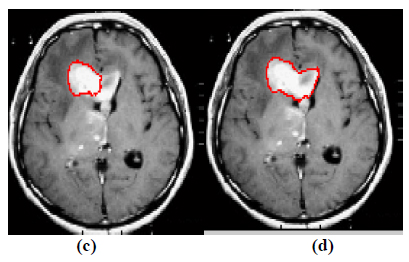

The experiment is conducted using brain web and Digital Imaging Communications in Medicine (DICOM) database [27, 28]. These database consists of T2 weighted MR images of sizes with tumor history. Pre-processing of an original MR image is an important step before applying the segmentation algorithms. In this case, the original MR image is pre-processed by applying median filter. Median filter removes salt and pepper noise which is very common in MR images of the brain. After removing the noise, wavelet transform is applied for multiresolution analysis to enhance the features of the image. Then, spatial FCM technique is applied to the multiresolution image. This technique minimizes search area to a very small region by creating cluster number k parameter for termination and max iteration values. Finally, these tumor clusters are segmented by level set evolution algorithm [29-39]. The following experimental results demonstrate the segmentation process used in the proposed methodology. In this experiment, two MR images having tumor in different locations of the image were selected to test the proposed segmentation algorithm. In Fig. (3), the original image and contour initialization for MR image 1 is shown. The contour evolution and final segmentation are depicted in Fig. (4). Similarly, Fig. (5) shows the original MR image 2 and the initial contour position. As the iteration values increases, the contour evolves towards the tumor boundary.

The qualitative results of the proposed method show that, the convergence of the contour towards the object boundary is very accurate and rate of convergence of the contour using level sets method is better than the traditional active contour models. The quantitative analysis is also carried out for the proposed technique using various performance measures.